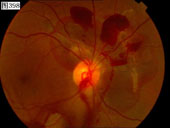

337 338 339 340